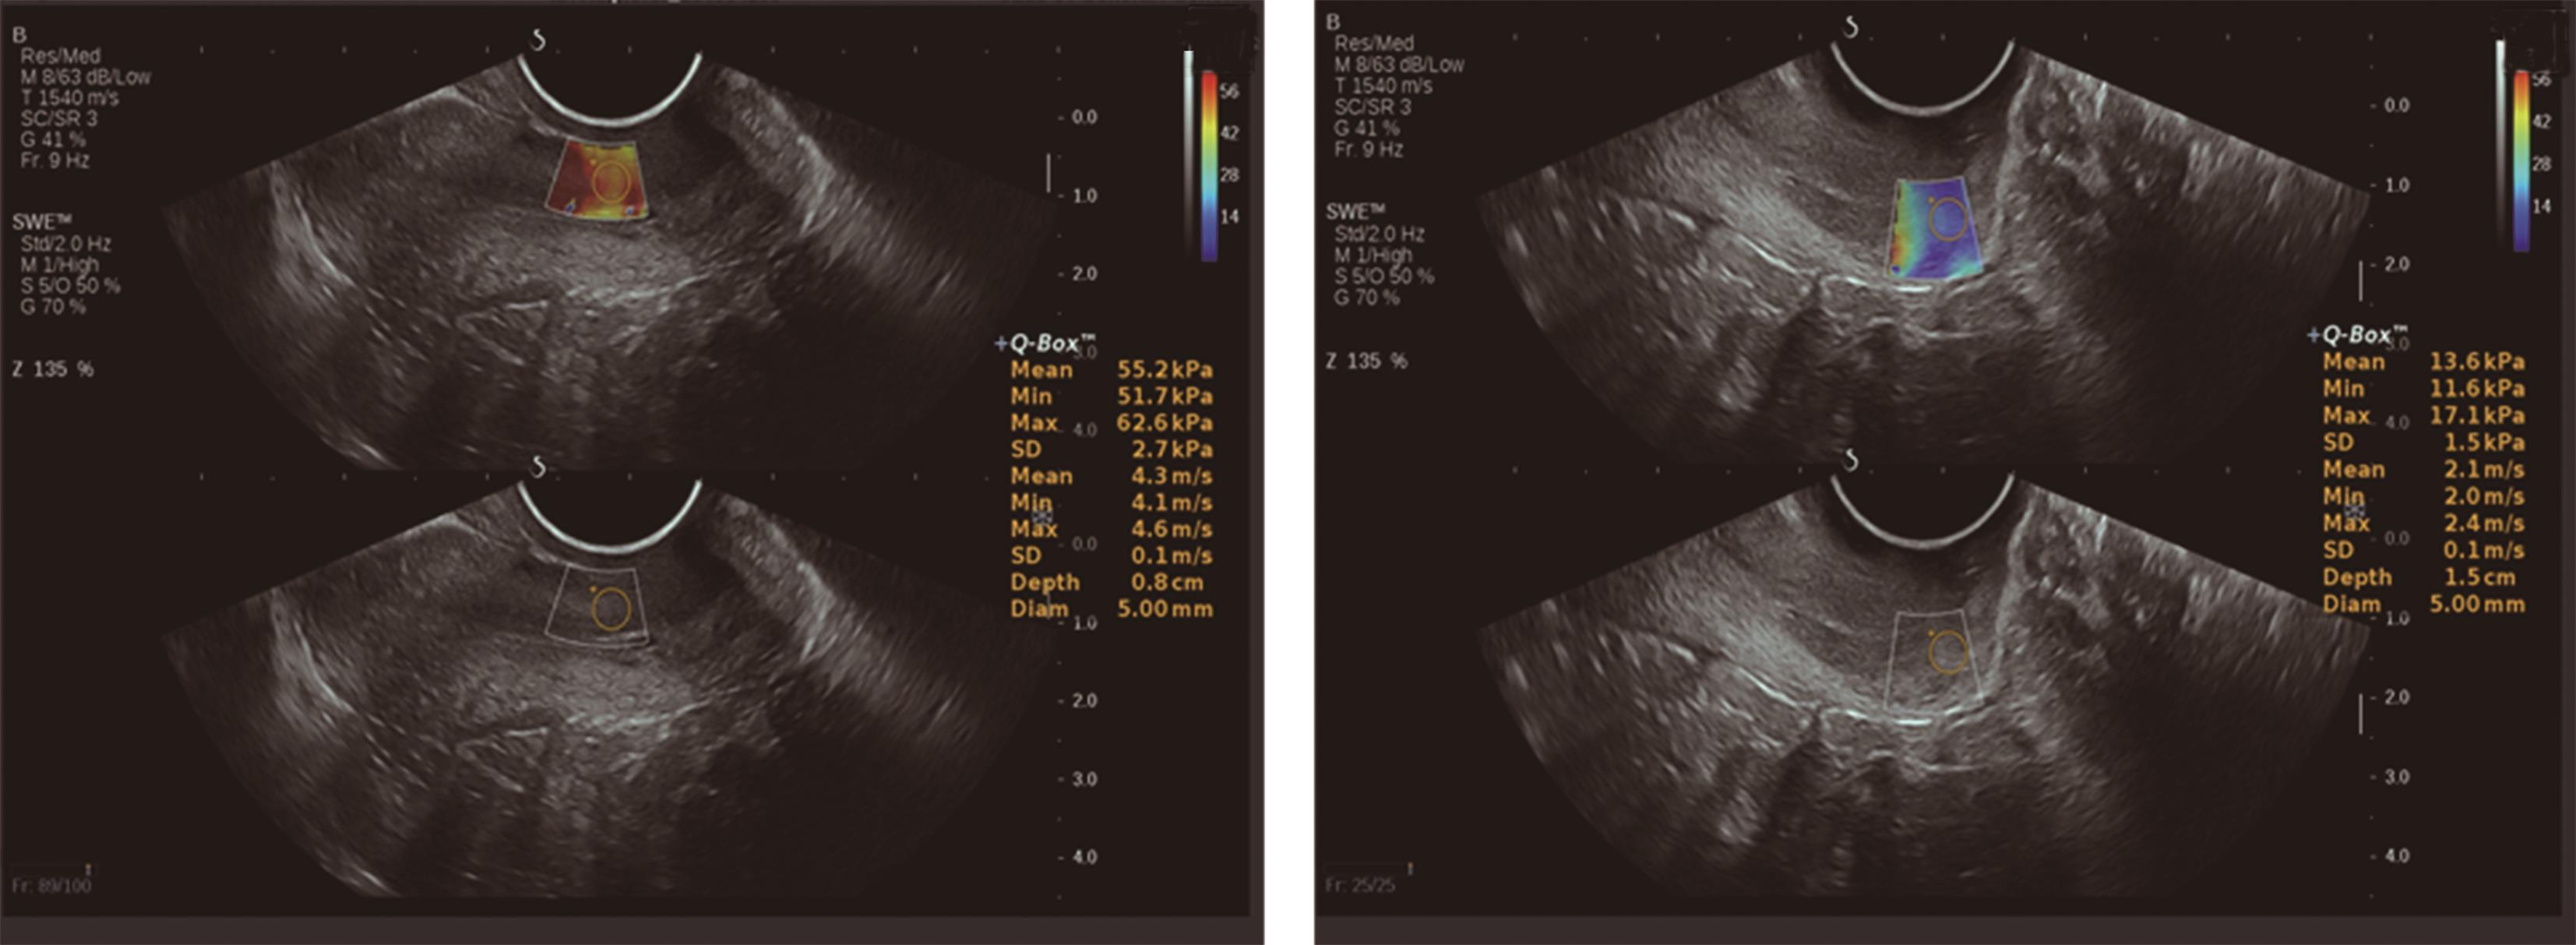

• 剪切波弹性成像测量宫颈硬度的可重复性研究

2023, 48(5):587-590. DOI: 10.13406/j.cnki.cyxb.003223

摘要 (100) HTML (44) PDF 1.18 M (212) 评论 (0) 收藏

摘要:目的 评价剪切波弹性成像(shear wave elastography,SWE)测量育龄期健康未育女性宫颈杨氏模量值的可重复性。方法 由同一名接受过SWE检测培训的高年资医师于同一天不同时间点,前后2次对100名处于育龄期但未育的健康女性宫颈行剪切波弹性成像,测量时选取宫颈4个位点:内口前唇(anterior lip of the inner mouth,IA)、内口后唇(posterior lip of the inner mouth,IP)、外口前唇(anterior lip of the outer mouth,EA)及外口后唇(posterior lip of the outer mouth,EP),获取育龄期健康未育女性宫颈杨氏模量值。使用组内相关系数(interclass correlation coefficient,ICC)评价检查者内可重复性,同时绘制Bland-Altman散点图评价测量一致性。结果 宫颈4个测量位点的前后2次测值均无统计学差异(P>0.05);宫颈IA、EA、EP处杨氏模量值的组内相关系数分别为0.828、0.785、0.768,提示组内可重复性非常好;宫颈IP处杨氏模量值的组内相关系数为0.632,提示组内可重复性好;Bland-Altman散点图提示SWE测量宫颈4个位点杨氏模量值的组内一致性均为好。结论 SWE可用于宫颈硬度的测量,且在宫颈不同位点均具有良好的可重复性与一致性。